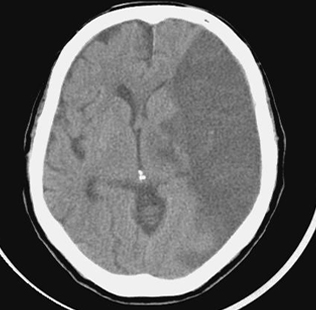

수술로 대뇌동맥이 심하게 좁아지면 스텐트나 경동맥내막절제술을 통해 동맥경화 자체를 없앨 수 있다.

혈전 용해제는 약물 치료에 사용됩니다. 뇌의 막힌 혈관에 혈전용해제를 도포하여 혈전을 녹이는 치료법입니다. 동맥 내 및 정맥 내 투여의 두 가지 방법이 있습니다. 동맥내 투여 방식의 장점은 즉시 효과를 볼 수 있다는 것이지만 단점은 시간과 노동력이 많이 든다는 점이다. 뇌졸중 후 3시간 이내에 사용할 수 있는 정맥주사법은 간편하다는 장점이 있지만 즉시 확인이 어렵다는 단점이 있다.

또 다른 약물 치료는 해열제입니다. 플라빅스, 아스피린, 티클리드, 프리탈은 혈전이 혈관벽에 형성되는 것을 방지하는 약물입니다. 따라서 항응고제가 사용됩니다. 뇌색전증으로 인한 뇌경색이나 심장병으로 인한 박리 시 혈액 응고를 멈추는 데 사용합니다.